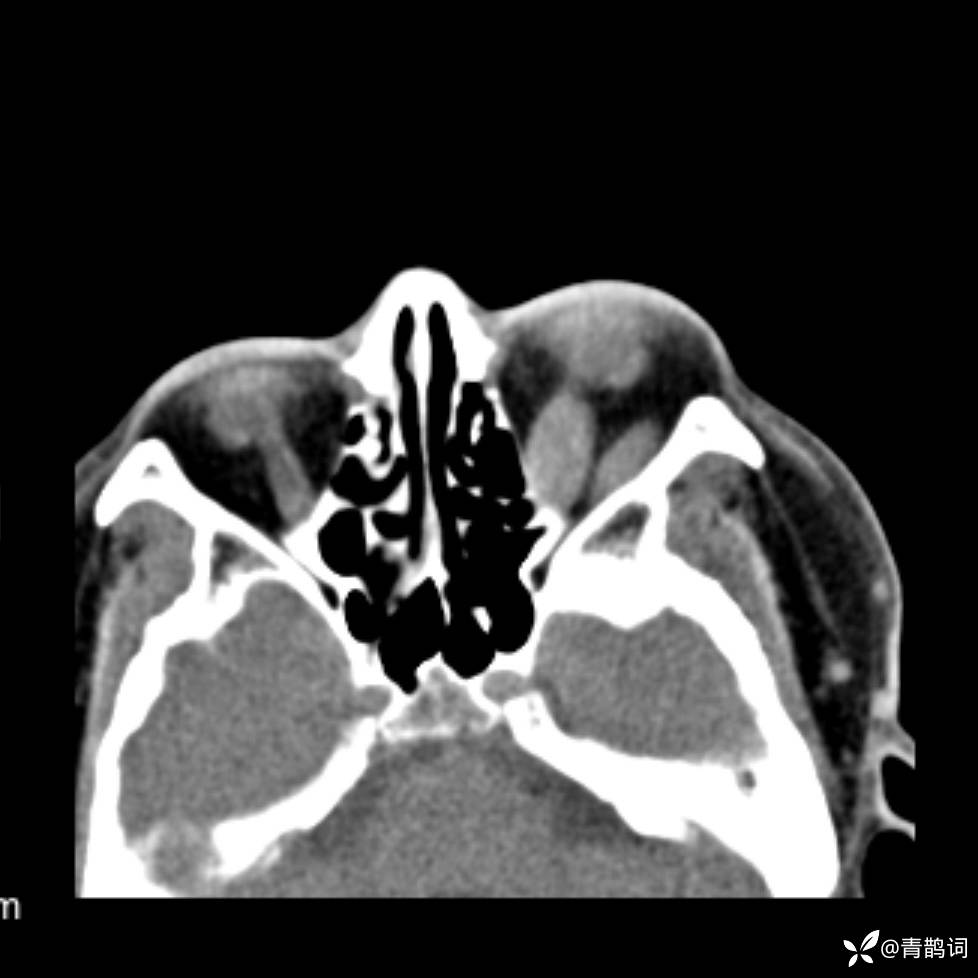

患者年龄:30岁。

患者性别:男。

简要病史:左颜面部肿胀2年,反复咳嗽咳痰,逐渐加重。

结合病史及影像学表现,期待评论区各位老师各抒己见~